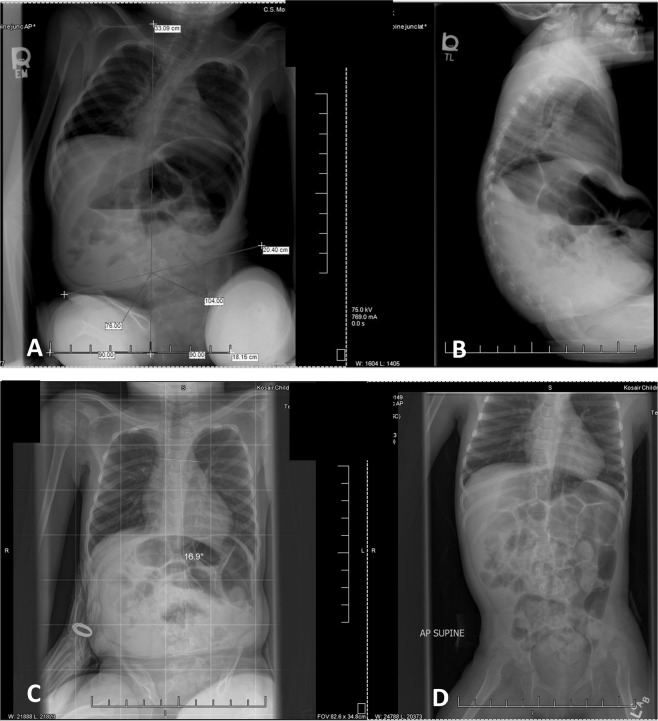

Fig. 7. Spine x-rays diagnostic for scoliosis.

Spine X-rays at age 6 years 1 month (a, b) and 6 years 5 months (c, d). At 6 years 1 month when imaged in sitting without request for active upright posture, she demonstrated a pelvic tilt of 14° and a spinal curve of 57° (a) as well as kyphotic posture (b). Four months later she was imaged again, this time she was verbally coached to “sit up tall” and use her arms to assist. She demonstrated a 16.9° spinal curve (c), the curve was also assessed in supine without external support (d) also resulting in a 17° curve.